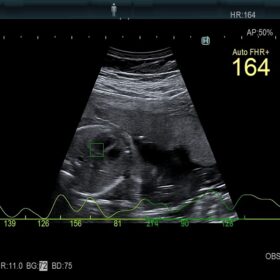

Women’s Health

Be equipped for breast pathologies and fetal assessment.

- Highly sensitive colour mode to replace contrast agents

- Doppler measurements from two gates in same heart cycle

- Advanced vessel and blood flow analysis tools